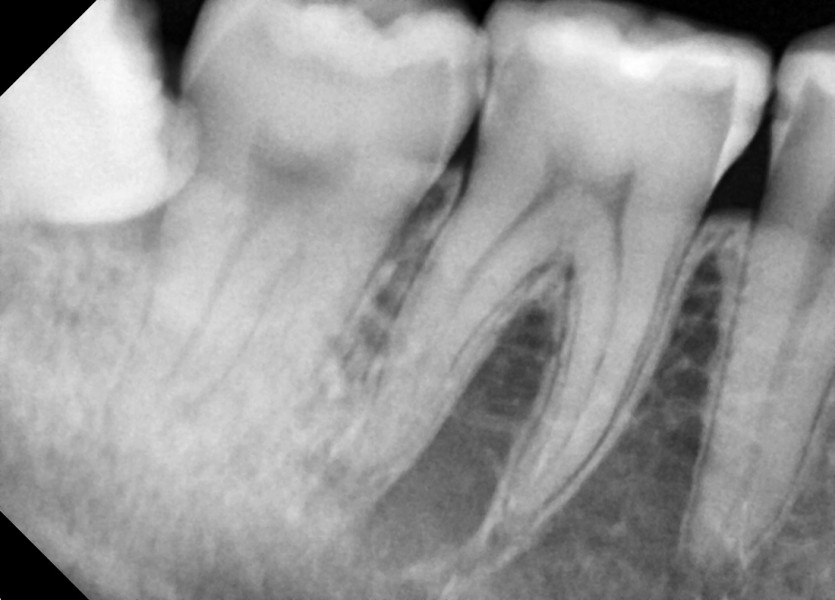

#18,48 사랑니 발치

구강 외과 전문의가 당일 발치했습니다.